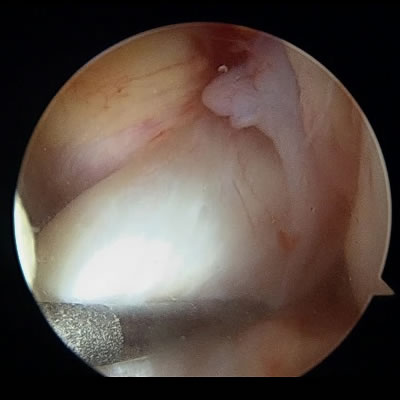

腱板修復術(肩腱板断裂)

関節鏡で肩関節の中を確認し、細い処置具や糸の着いたアンカーを使って、腱板を元の位置へ修復します。